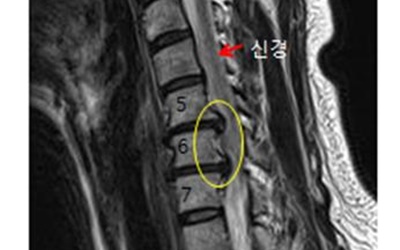

이를 의학계에서는 경추 추간판 탈출증이라고 한다고 하고요. 경추와 뼈들 사이에 존재하고 있는 물렁한 뼈조직이 있으며, 이를 디스크라고 하더라고요. 문제가 되는 것은 이 디스크가 외부로 탈출해서 신경을 압박하면서 통증이 시작되어요.

목을 통해서 관련되어 있는 팔과 어깨 손의 신경이 목디스크 증상으로 인하여 감각이 이상이 발생하거나 무뎌지고 해서 형성되는 증상으로 목디스크 증상은 거의 퇴행성 질환으로 나이가 40대 이상에서 더디게 증상이 구성되는 경우가 흔해요. 하지만 꼬이게된 생활습관이나 오랜 시간 앉아있으면 비집고 나온 수핵이라고 하는 것이 척수를 압박하게 되고 있는데 척수가 신경을 누르게 되어 통증을 느끼게 되는 것이고요.

목디스크 증상은 거의 퇴행성 질환으로 4050대에서 천천히 증상이 생기는 경우가 두둑한데요. 꼬이게된 생활습관이나 오랜 시간 앉아있으면 비집고 나온 수핵이 척수를 압박해 신경을 누르게 되어 통증을 즐기고요. 손에 힘이 빠지고 저리다가, 다리까지 힘이 빠져 걷기 어려운 보행장애가 나타나게 돼요.